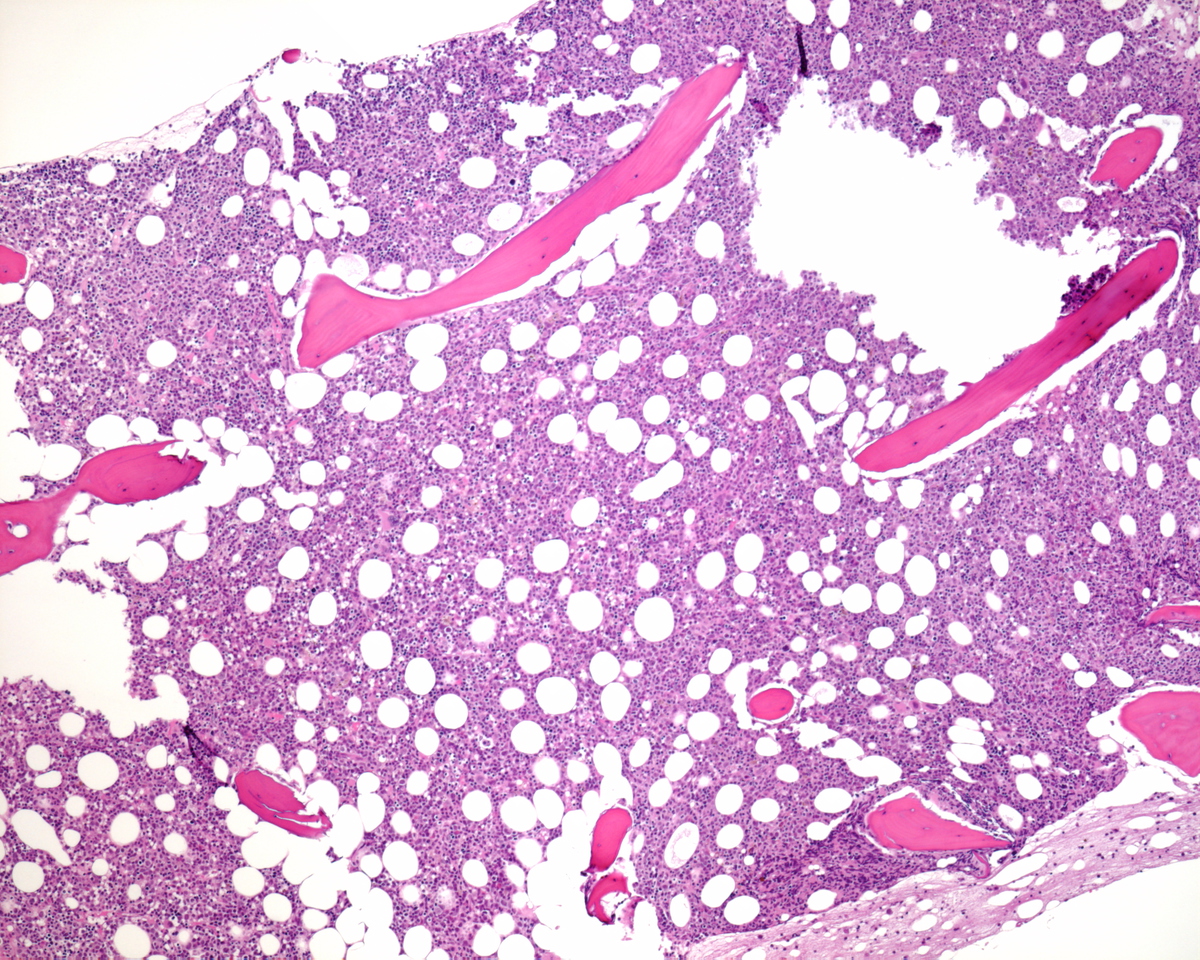

Bone marrow aspirate direct and particle smears, blood clot, right iliac crest biopsy and accompanying peripheral blood smear were received. The peripheral blood, direct and particle smears were stained with Wright-Giemsa stain. The clot and core biopsy were fixed in 10% buffered formalin and the biopsy was decalcified in formic acid bone decalcifier (Immunocal). The peripheral blood smear shows pancytopenia with anisocytosis, and a leukoerythrobastic reaction. No Auer rods are noted on the circulating blasts. Occasional neutrophils appear dysplastic with hypogranulation and hyposegmentation. The bone marrow smears were hemodilute and showed no significant dyspoiesis in the erythroid and granulocytic series. Megakaryocytes were predominantly small sized and left shifted. The decalcified bone marrow biopsy is hypercellular for age with markedly increased immature precursors with prominent nucleoli. The few fully mature megakaryocytes present do not show morphologic features associated with ET. Increased numbers of micromegakaryocytes as well as small, left shifted megakaryocytes are present.

Immunohistochemical stains showed marked increase of megakaryocytes, including numerous small, monolobated forms, which are strongly positive for CD61. CD34 and CD117 highlight increased immature cells, approximately 10% of the nucleated marrow elements. Reticulin shows mild diffuse increase in fiber deposition. An iron stain shows adequate stainable iron. Immunophenotyping by flow cytometry reveals approximately 7% of the total gated events in the dim CD45 positive gate, which coexpress CD34, CD117 and myeloid antigens. A subset of the cells coexpress CD41 and CD61 indicating megakaryocytic lineage.

| Core BX low power | ![]() |

| Core BX high power 40X | ![]() |